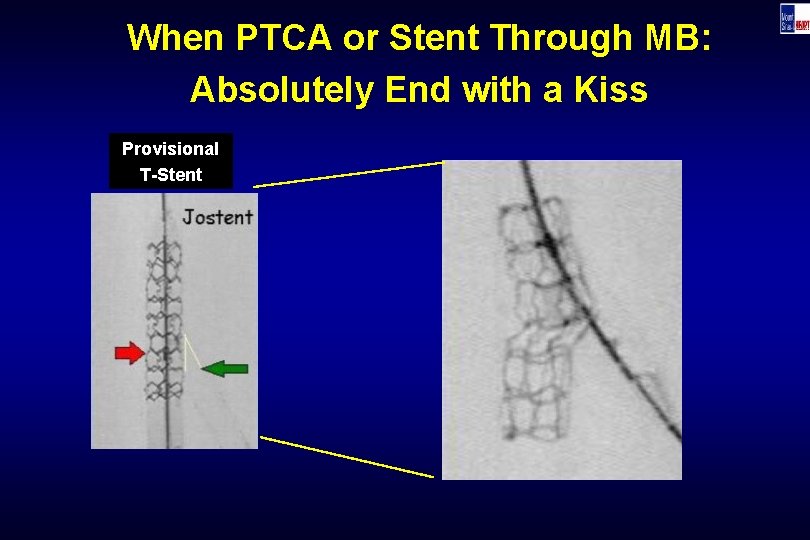

When PTCA or Stent Through MB: Absolutely End with a Kiss Provisional T-Stent